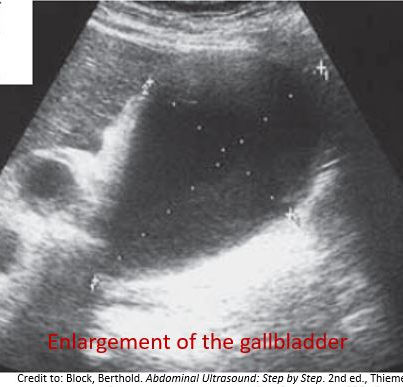

Normal VS Abnormal Appearances